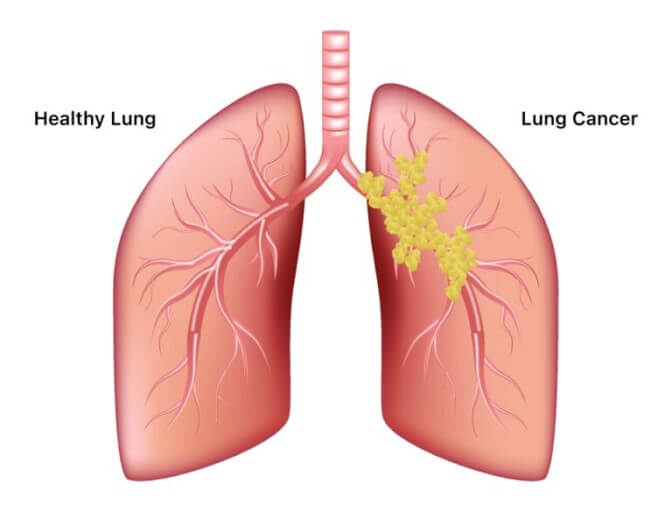

폐암의 초기증상은?

폐암은 초기에는 증상이 나타나지 않기 때문에 진단하기 어려운 암입니다. 그러나 폐암이 진행됨에 따라 다음과 같은 증상이 나타날 수 있습니다.